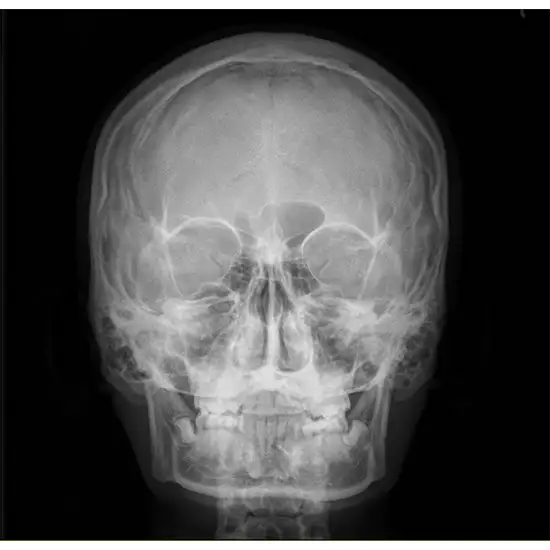

Zygomatic arch X-rays show cheekbone length. The zygomatic arch comprises the zygomatic bones, temporal bone, skin, and muscles.

The zygomatic arch is the third most commonly broken facial bone, and most people who break it are men. Early stabilization is essential to ensure that the body looks good and works well.